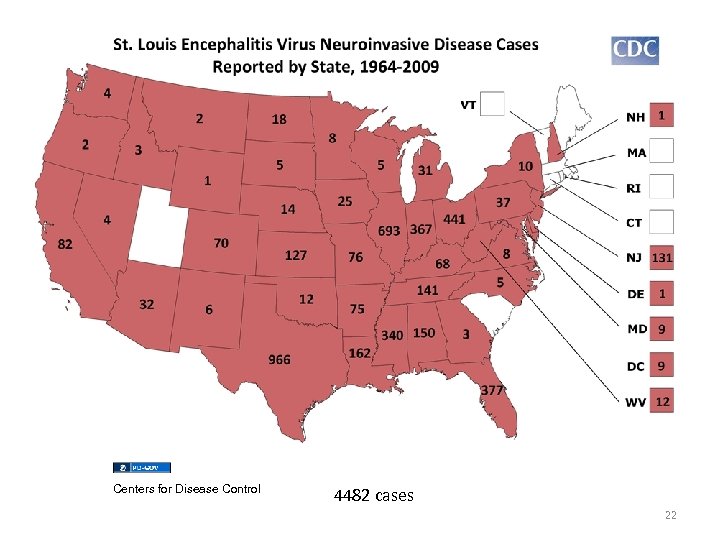

Centers for Disease Control 4482 cases 22